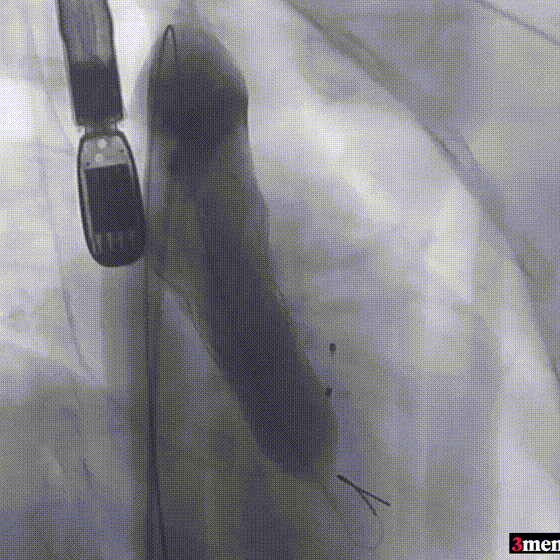

患者全麻后,右侧股动脉建立主入路,主动脉根部造影显示主动脉瓣明显钙化。心室内轻微反流,主动脉及心脏情况整体较为稳定。直头导丝跨瓣后,在超硬导丝支撑下,瓣膜输送系统顺利跨瓣。在180次/分快速心室起搏下,确定降压至50mmHg后选择18mm球囊进行预扩张。在球囊扩张后,该患者血压未见升高,随即进行胸外按压,同时根据术前评估及球囊预扩情况,选取直径23mm瓣膜果断快速进行瓣膜定位并释放。瓣膜释放后患者心律和血压趋于平稳。

球囊预扩

瓣膜定位并行胸外按压

瓣膜释放至工作位

瓣膜脱钩